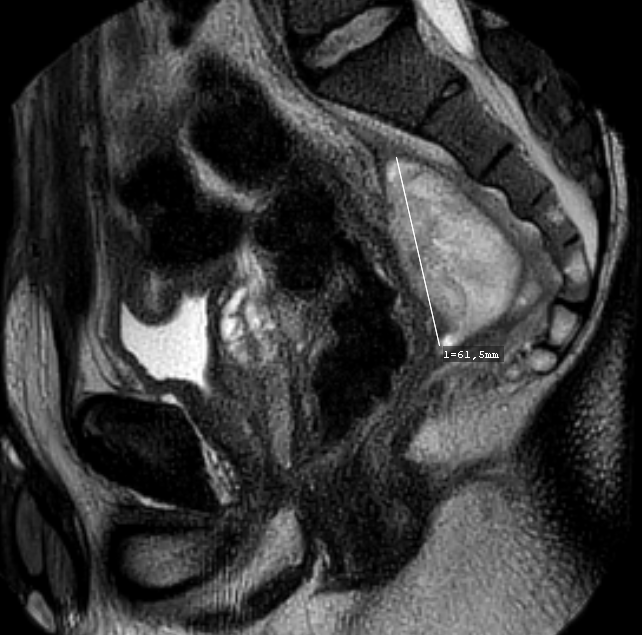

The doppler-guided transanal hemorrhoidal dearterialization (DG-THD) is a well-established and validated minimally invasive procedure for the treatment of symptomatic hemorrhoids. As compared to the excisional technique, DG-THD has the advantage of being associated with less post-operative pain and do not compromise the anatomy or the physiology of the anal canal. Our objectif is to describe the first case of perianal abscess following DG-THD. We report perianal abscess in a previously healthy 32-year-old male patient, who underwent DG-THD for grade II hemorrhoids, as an outpatient procedure. One week later, the patient complained of persistent pain in the right iliac fossa and hypogastrium. CT-scan showed a peri-rectal fluid collection with gas bubbles and peripheral enhancement. MRI was obtained after first attempt of elective drainage, showing increase of the collection diameter without any fistula, which prompted a surgical exploration and drainage. Multi sensitive E. coli was found on culture. Post-operative recovery was slow but favourable. To the best of our knowledge, no previous report of perianal abscess following DG-THD has been described in the literature, which we believe in our case to be of haematogenous origin.